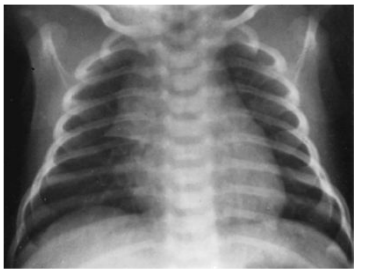

26.本題附圖之嬰兒胸部X光可看到什麼?

(A).胸腺(thymus) (B).心臟擴大(cardiomegaly) (C).肺炎(pneumonia) (D).肺出血(pulmonary hemorrhage)